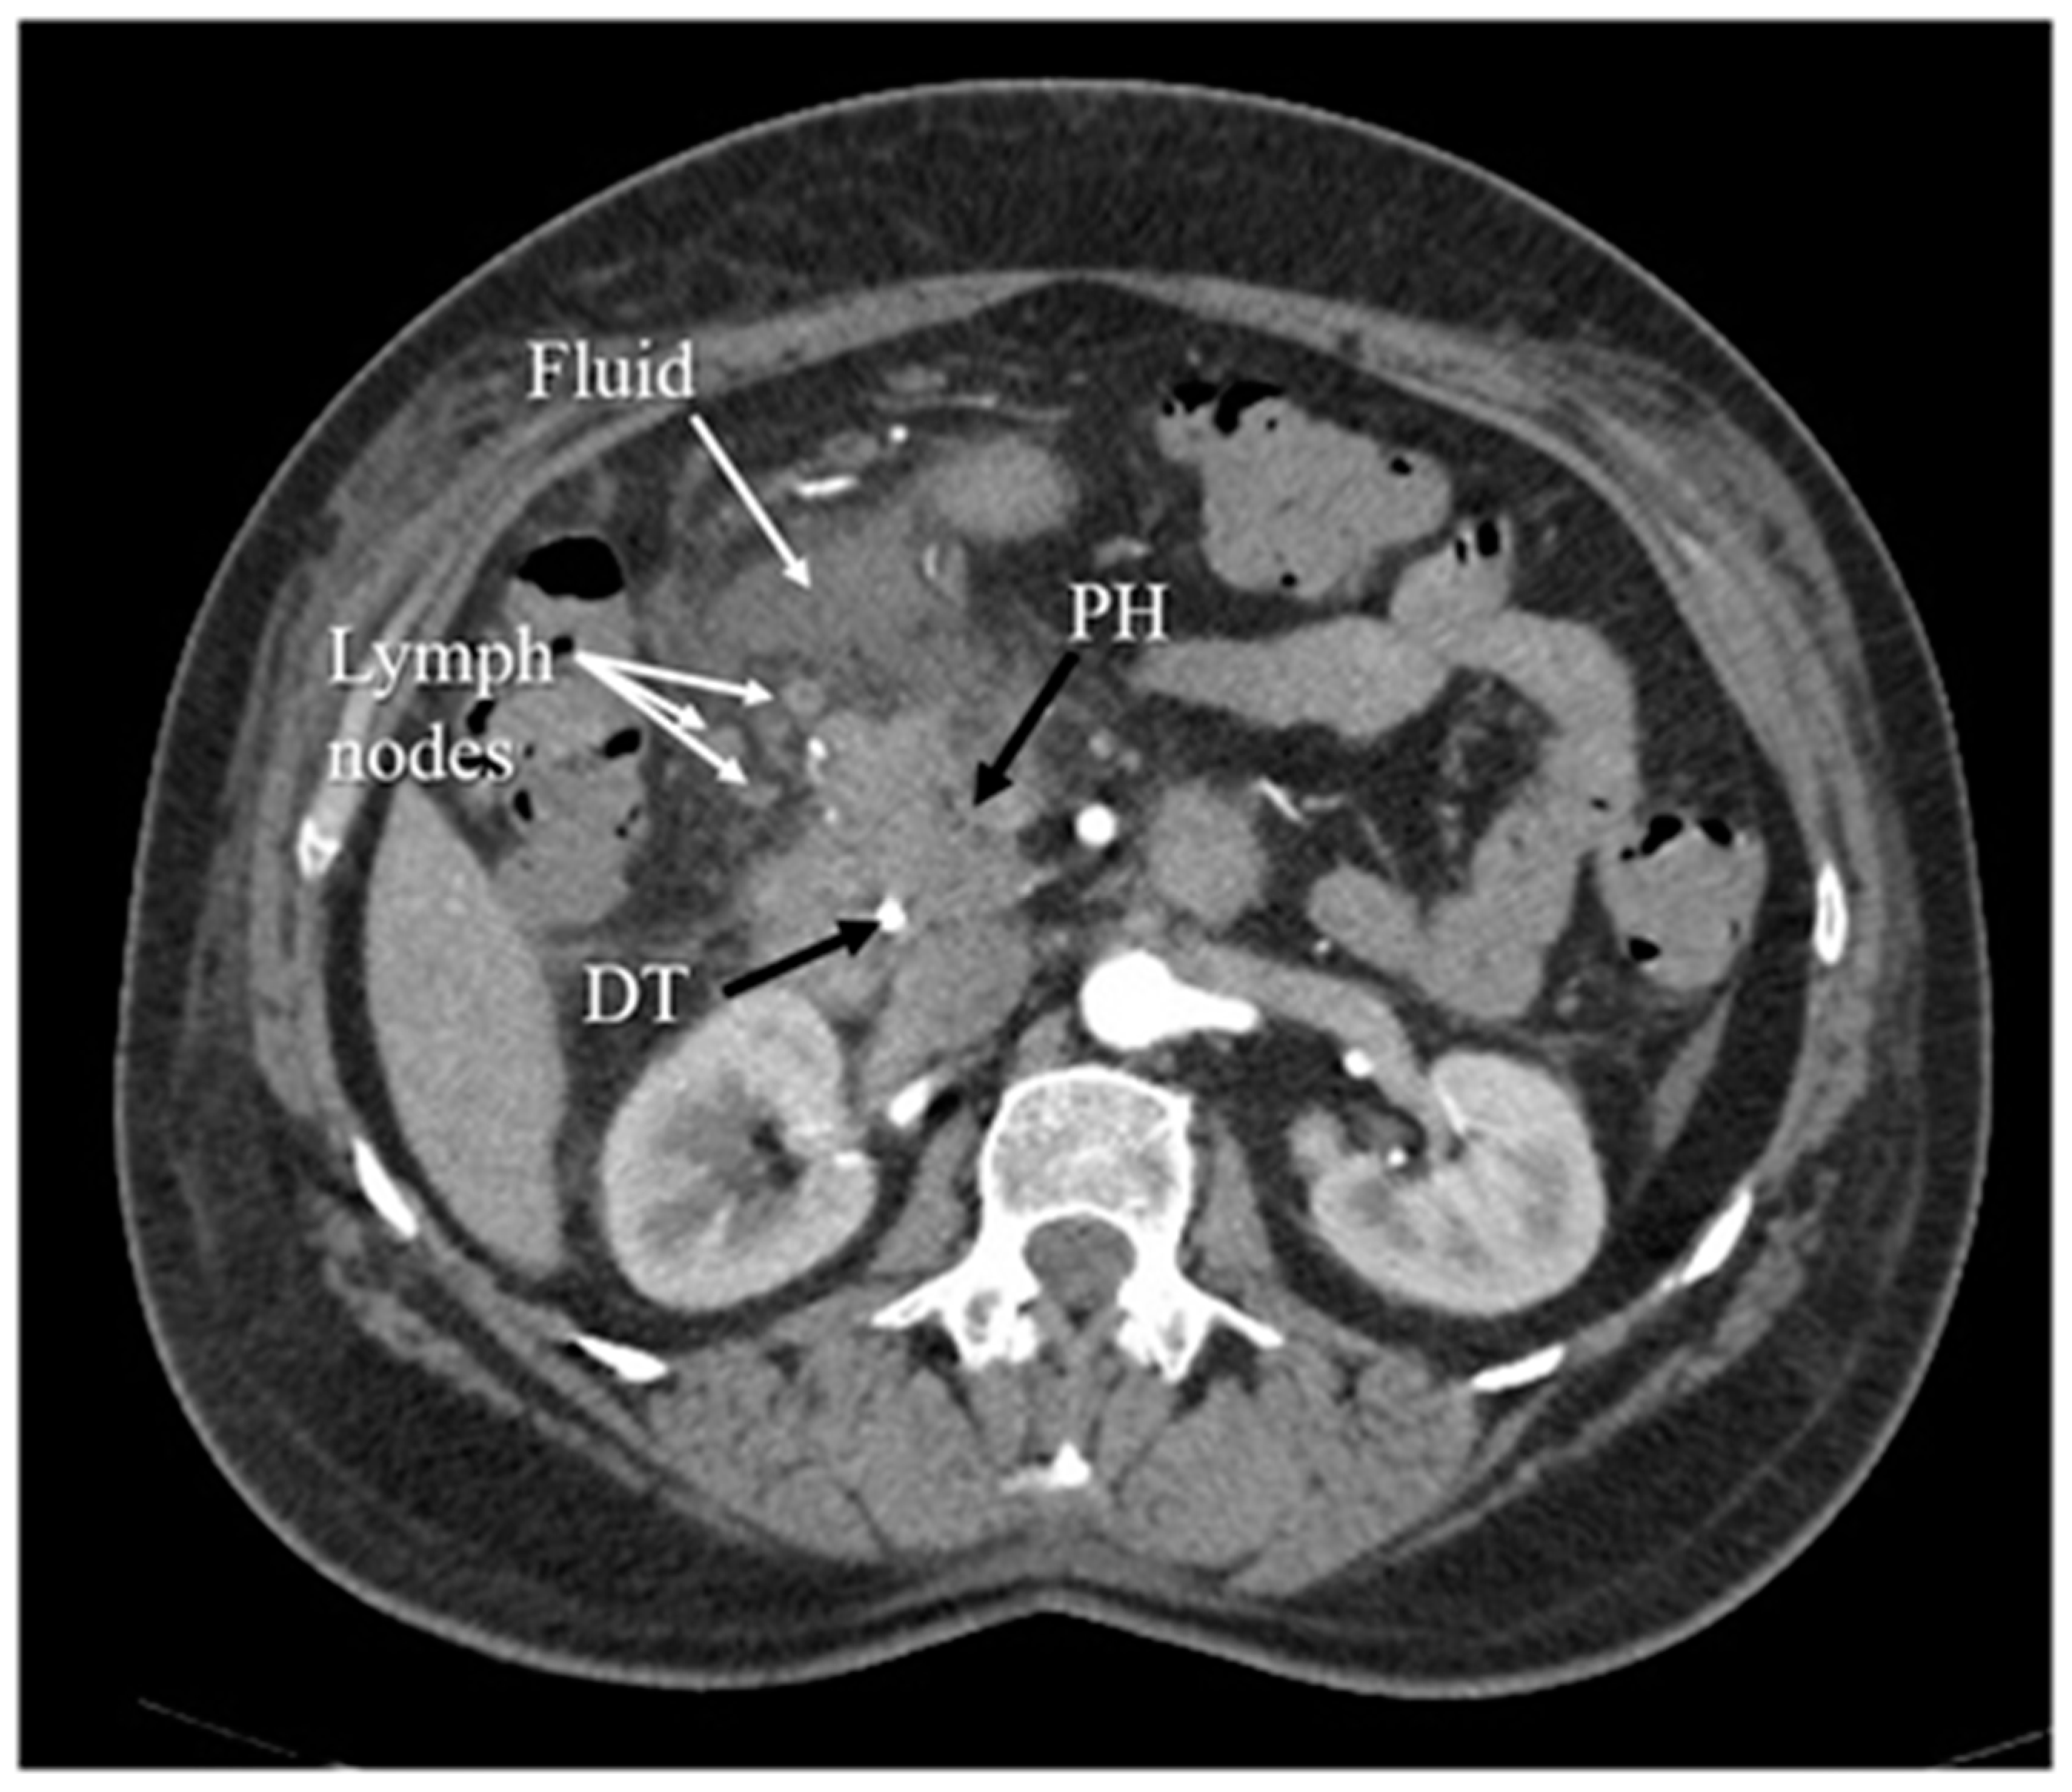

3.5. Computed Tomography

- Raghuwanshi, S.; Gupta, R.; Vyas, M.M.; Sharma, R. CT evaluation of acute pancreatitis and its prognostic correlation with CT severity index. J. Clin. Diagn. Res. 2016, 10, TC06. [Google Scholar] [CrossRef]

- Balthazar, E.J. Acute pancreatitis: Assessment of severity with clinical and CT evaluation. Radiology 2002, 223, 603–613. [Google Scholar] [CrossRef]

- Balthazar, E.J.; Robinson, D.L.; Megibow, A.J.; Ranson, J.H.C. Acute pancreatitis: Value of CT in establishing prognosis. Radiology 1990, 174, 331–336. [Google Scholar] [CrossRef]

- Mortelé, K.J.; Mergo, P.J.; Taylor, H.M.; Wiesner, W.; Cantisani, V.; Ernst, M.D.; Kalantari, B.N.; Ros, P.R. Peripancreatic vascular abnormalities complicating acute pancreatitis: Contrast-enhanced helical CT findings. Eur. J. Radiol. 2004, 52, 67–72. [Google Scholar] [CrossRef]